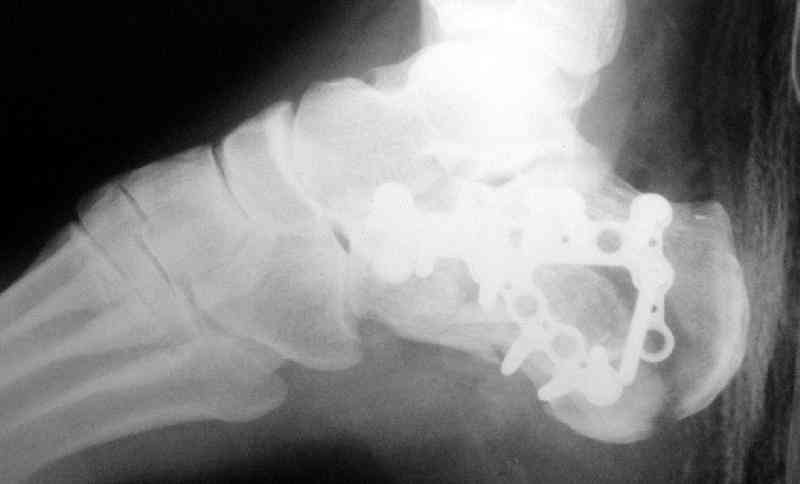

Пяточной пластиной

Открытый и закрытый способы лечения.

MOST OF MY COLLEGUES WOULD OPEN IT LATERALLY( a flap) and having a proper reduction would put a plate.

Имея какой-то опыт остесинтеза пяточной кости пластинами пришли к выводу - где есть альтернатива лучше без нее, где нет значит пластина и долгие переживания в ожидании очередной перевязки. Может нам так не везло, но и одного некроза( слава богу без остеомеилита) достаточно, чтобы призадуматься.